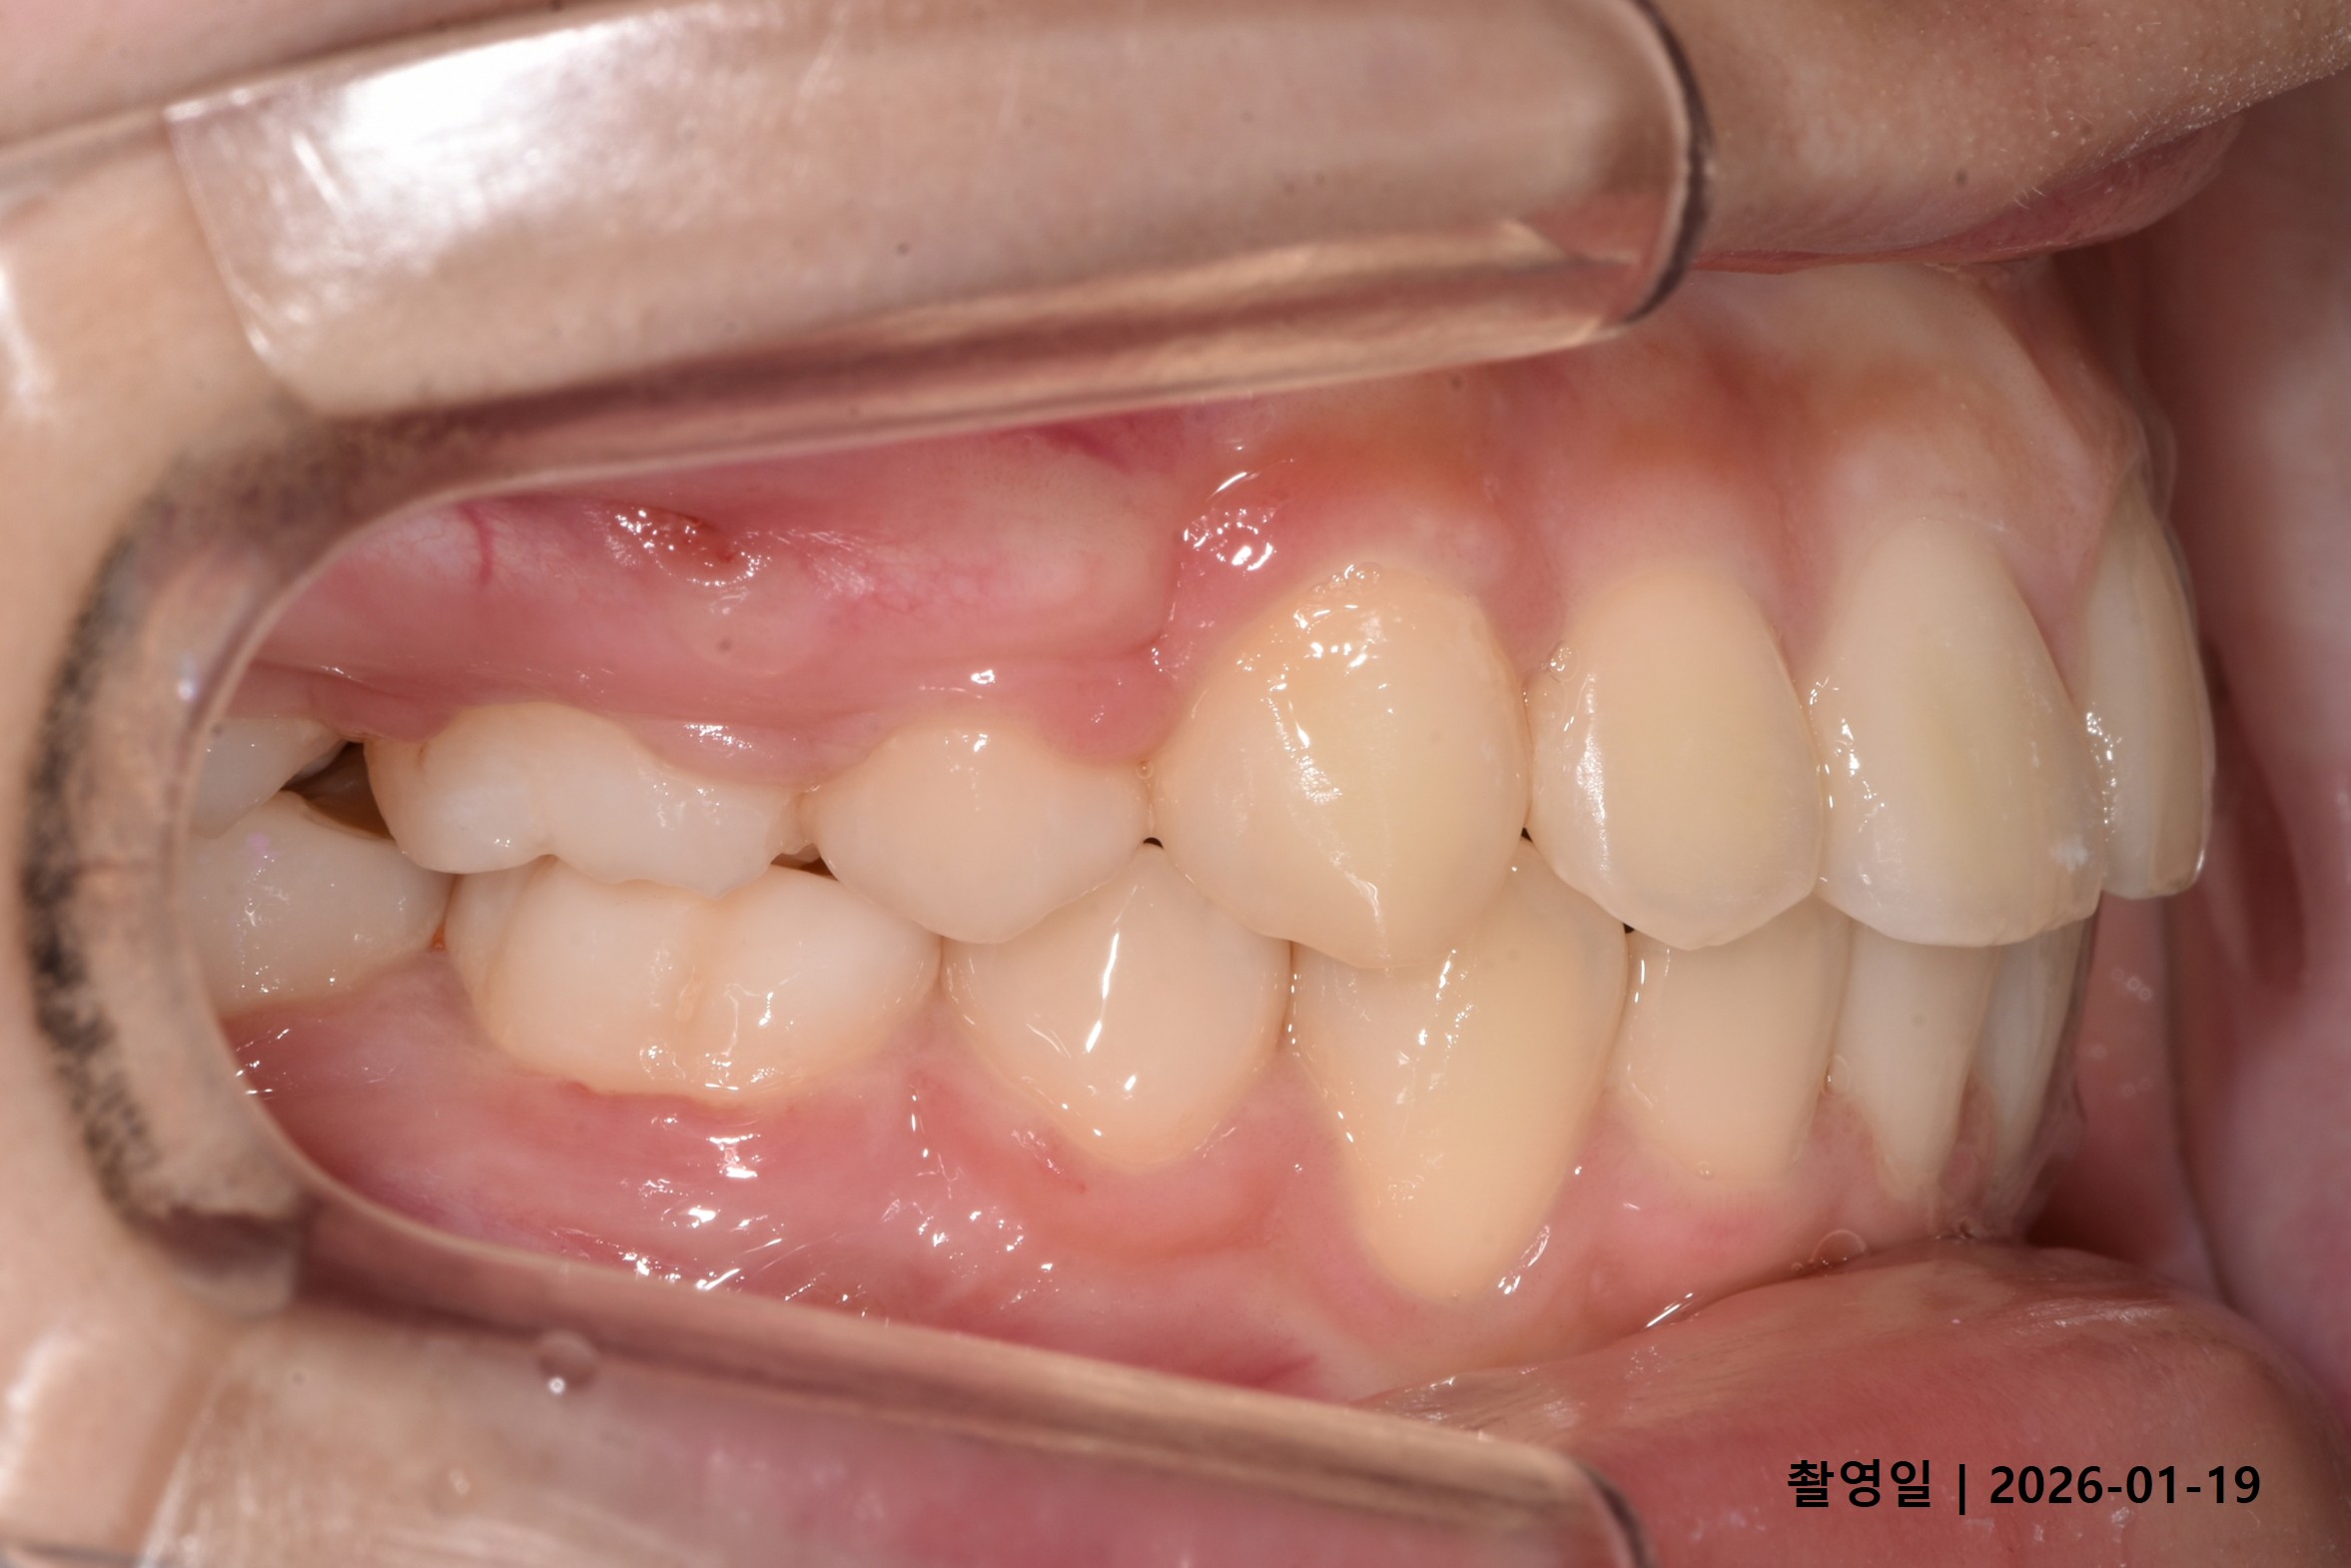

Case 2

- 24세 여성

- 상하악소구치 발치

- 치료기간 2년 1개월

치료 전

치료 후